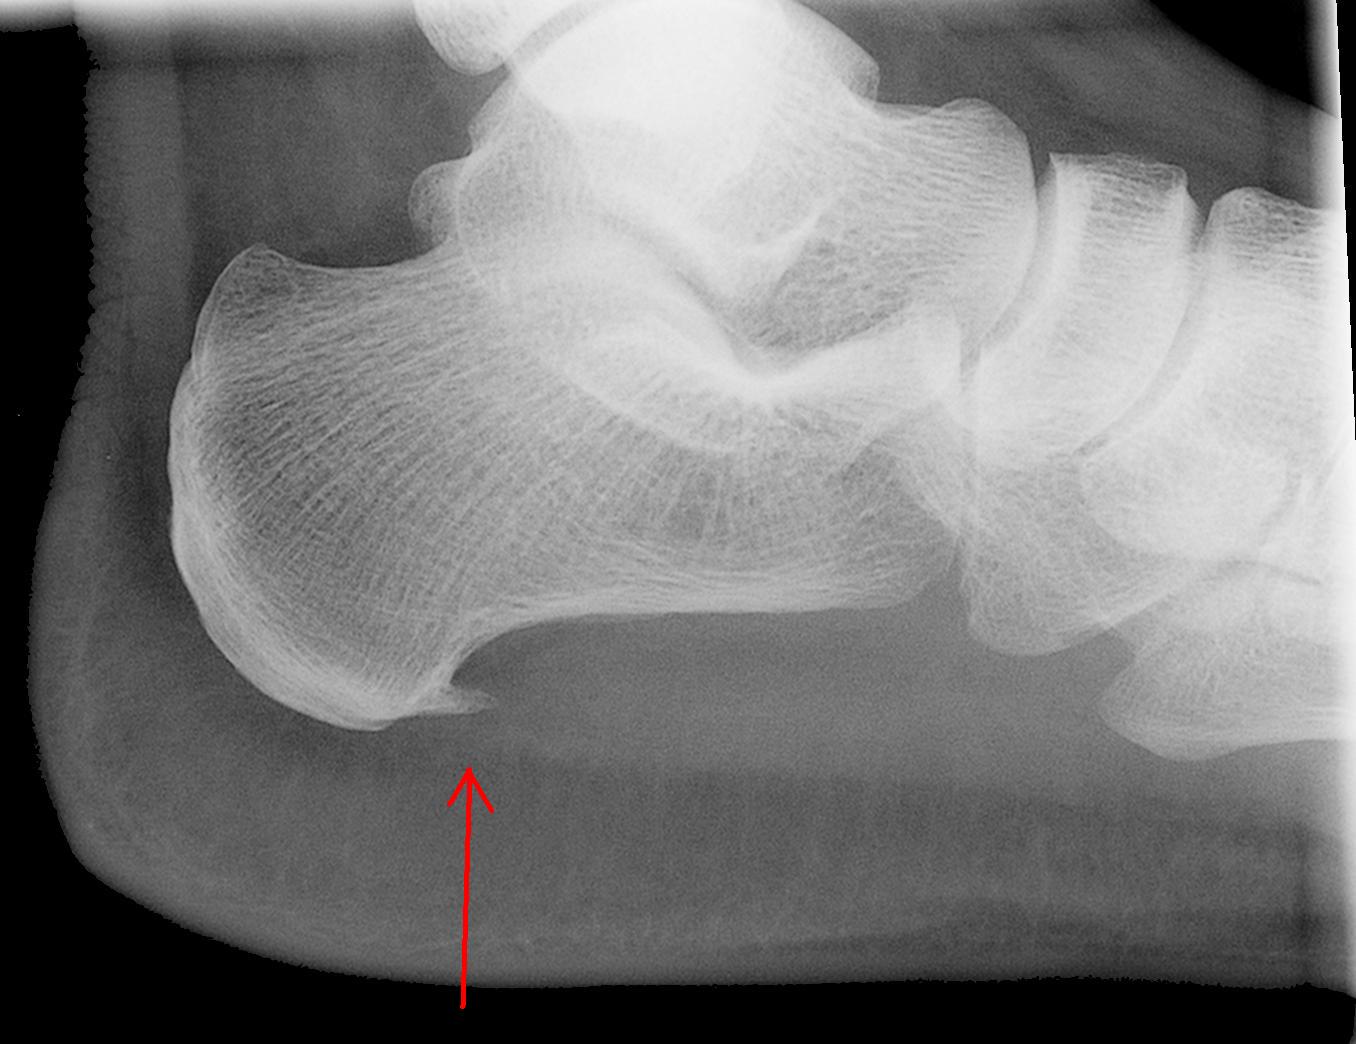

Pentru refacerea completa si corecta a osului este esential ca medicul ortoped sa alinieze perfect capetele osului fragmentat. Atentie, procesul de refacere a osului debuteaza imediat de la fractura. Supravegherea vindecarii osului se realizeaza prin intermediul radiografilor osului fracturat, radiografii care ajuta medicul ortoped sa vada daca procesul de vindecare decurge corect, daca osul s-a deplasat sau nu din pozitia corecta.

- A treia etapa consta in aparitia si inceputul formarii unui nou os, respectiv osul nou denumit stiintific calus. Acest os nou se formeaza pe amplasamentul vechiului os rupt, linia de ruptura disparand.

- In a patra etapa calusul sau osul nou evolueaza si se maturizeaza, avand densitatea si fiind mai puternic decat vechiul os.